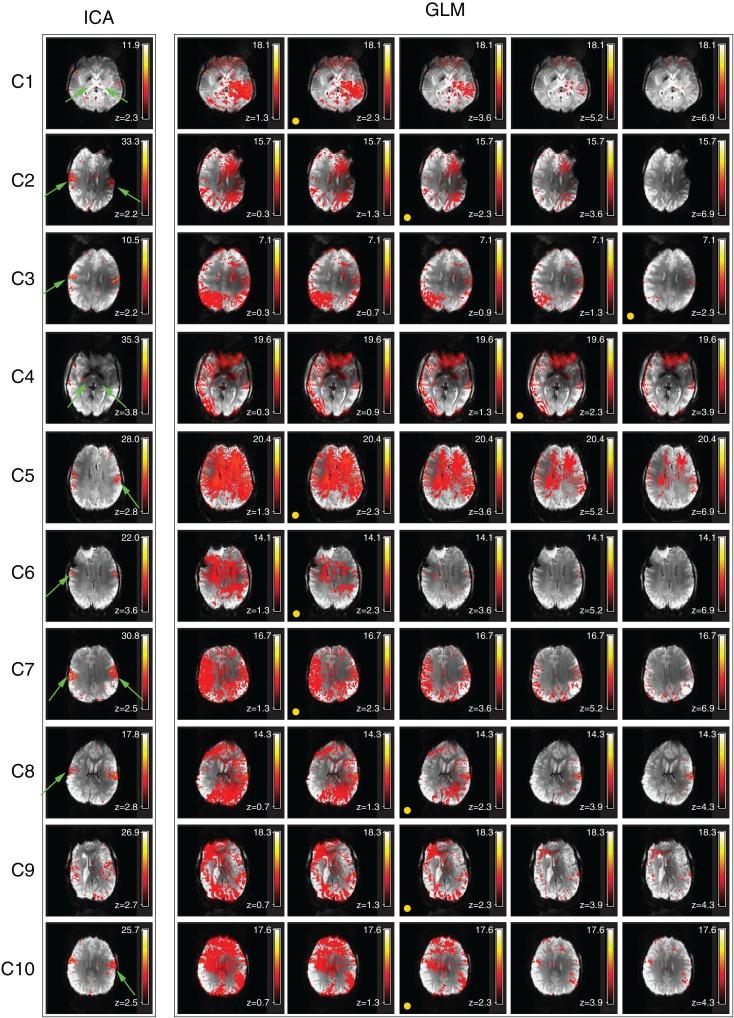

Increased BOLD sensitivity at 7 T offers the possibility to increase the reliability of fMRI, but ultra-high field is also associated with an increase in artifacts related to head motion, Nyquist ghosting, and parallel imaging reconstruction errors. In this study, the ability of independent component analysis (ICA) to separate activation from these artifacts was assessed in a 7 T study of neurological patients performing chin and hand motor tasks. ICA was able to isolate primary motor activation with negligible contamination by motion effects. The results of General Linear Model (GLM) analysis of these data were, in contrast, heavily contaminated by motion. Secondary motor areas, basal ganglia, and thalamus involvement were apparent in ICA results, but there was low capability to isolate activation in the same brain regions in the GLM analysis, indicating that ICA was more sensitive as well as more specific. A method was developed to simplify the assessment of the large number of independent components. Task-related activation components could be automatically identified via these intuitive and effective features. These findings demonstrate that ICA is a practical and sensitive analysis approach in high field fMRI studies, particularly where motion is evoked. Promising applications of ICA in clinical fMRI include presurgical planning and the study of pathologies affecting subcortical brain areas.

在 7T 下增加 BOLD 敏感度可以提高 fMRI 的可靠性,但超高场也与与头部运动、奈奎斯特鬼影和并行成像重建错误相关的伪影增加有关。在这项对进行下巴和手部运动任务的神经科患者的 7T 研究中,评估了独立成分分析(ICA)将激活与这些伪影分离的能力。ICA 能够隔离主要运动激活,而运动影响的污染可忽略不计。相比之下,这些数据的广义线性模型(GLM)分析结果受到运动的严重污染。ICA 结果显示出次级运动区、基底节和丘脑的参与,但在 GLM 分析中分离相同脑区的激活能力较低,这表明 ICA 更敏感也更特异。开发了一种方法来简化对大量独立成分的评估。通过这些直观有效的特征,可以自动识别与任务相关的激活成分。这些发现表明,ICA 是高磁场 fMRI 研究中一种实用且敏感的分析方法,特别是在诱发运动的情况下。ICA 在临床 fMRI 中的有前景的应用包括术前规划和研究影响皮质下脑区的病理学。